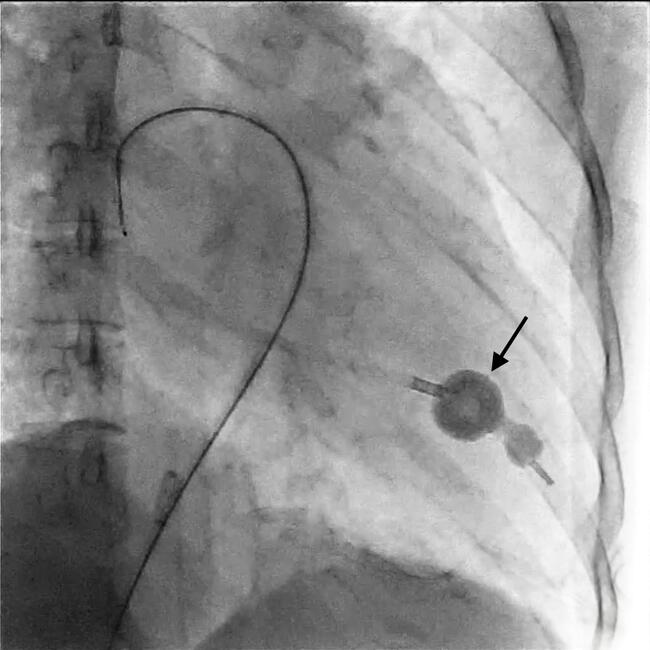

After informed consent, the patient was taken up for balloon mitral valvotomy (BMV). The calculated balloon size (height/10+10) was 25 mm; a 26-mm SYM balloon (Translumina) was prepared at 23 mm in view of severe subvalvular disease. After septal dilation, the balloon was crossed to the left ventricle with the reverse loop technique. During balloon inflation, the proximal balloon inflated before the distal balloon, which suggested the Impasse sign (Figure, Video). The balloon was deflated immediately, the mitral valve was recrossed again, and successful balloon dilation was done. The left atrial pressure decreased from 24 to 16 mm Hg, and mild mitral regurgitation was noted; henceforth, no further dilations were given. In this case, the operator felt that the impasse sign occurred due to entanglement of the distal balloon in the chordal apparatus.

The impasse sign portends severe mitral regurgitation in BMV. The operator should be aware of this possibility and, if the impasse sign is noticed, the operator should deflate the balloon immediately to avoid severe mitral regurgitation.